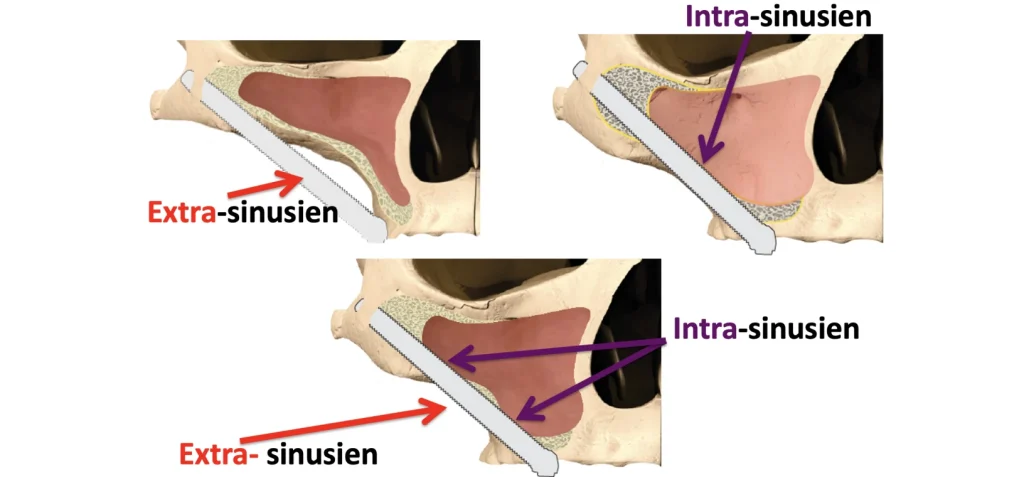

Le trajet de l’implant zygomatique dépend de l’anatomie et du volume des sinus. Il peut être à l’extérieur du sinus si le sinus est concave et de petit volume, dans le sinus si le sinus est convexe et volumineux ou à cheval. Les études cliniques actuelles ne montrent pas plus de nouvelles pathologies sinusiennes chez les patients ayant des implants zygomatiques dont le trajet est intra-sinusien.